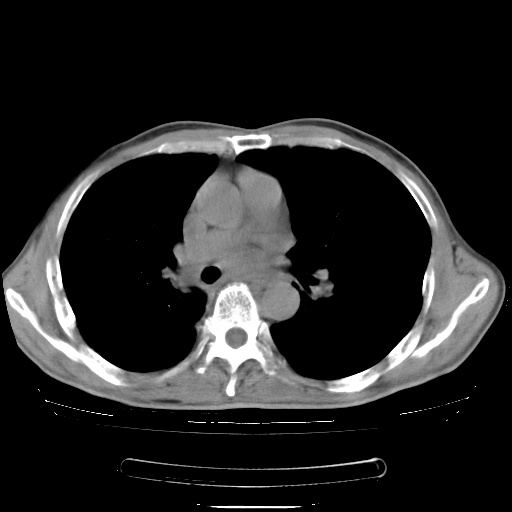

男性患者,63岁。右侧胸背部疼痛2月,加重一周。

考虑:右肺中央型肺癌并右肺下叶不张;两肺尖继发性肺结核。

还有纵隔多处肿大淋巴结及肋骨的改变、两肺多发结节灶。

右肺下叶支气管狭窄闭塞,右下肺不张,气管前间隙淋巴结肿大,两上肺散在分部粟粒灶,沿肺血管支气管束分部,血管支气管束走形较为光滑。考虑右肺中心型肺癌合并肺不张,纵隔淋巴结转移,两上肺癌性淋巴管炎

右肺下叶中心性肺癌并纵隔淋巴结转移,左侧肋骨转移。双肺上叶继发性结核表现。